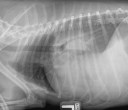

Maladie bronchique féline (asthme pour ne pas le nommer)